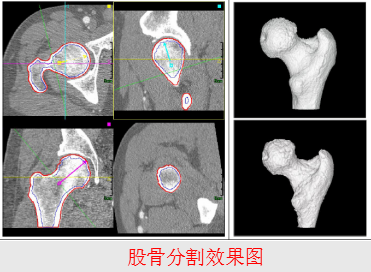

2、分割

根据目标物体特征,把图像划分为若干个互不相交的区域,使得这些特征在同一区域内,表现为一致性或相似性,在不同区域表现明显不同。

可辅助医生进行诊断和制定对病人的治疗方案;

用于医学图像的分析,如三维重建;

用于计算机引导于术,如外科手术的制定,病理的研究;

有利于数据的压缩和传输,提高在PACS和远程传输的应用。

骨密度测量

-

骨质疏松症

------骨密度降低所引发的主要病症

------高骨折风险

-

股骨近端和腰椎发生骨折的危险最高

-

欧盟: 每年约400,000例

------与年龄相关(骨折易发年龄:

女40%, 男13%, >50 岁)

骨密度测量(方法)

-

X射线摄片

-

光子吸收法

-

双能X射线吸收法

-

超声测量法

-

定量CT(Quantitative Computed Tomography, QCT)

QCT测量骨密度

对平片的手动测量

BMD = a × CTValue + b

对三维重建序列的测量

-----测量部位的分割

-----皮质骨与松质骨的分离

-----数值的测量